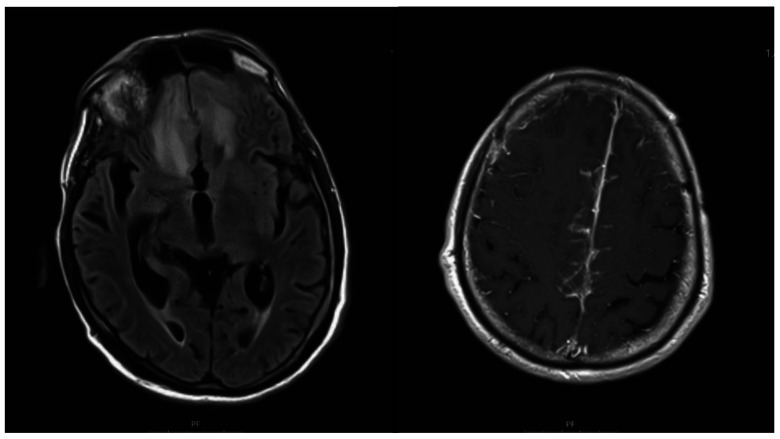

Prolonged cocaine inhalation can cause destruction of nasal mucosa and ethmoid sinuses and palate perforation, thus inducing cocaine-induced midline destructive lesions (CIMDL) that affect only a limited number of predisposed patients. CIMDL are an autoimmune necrotizing inflammatory phenomenon associated with the presence of atypical antineutrophil cytoplasmic antibody (ANCA). Patients complain of epistaxis, nasal obstruction, hyposmia, sinus infections, and facial pain. Protocol for the CIMDL diagnosis includes medical history, clinical examination, magnetic resonance imaging, laboratory tests, immunology and serology tests, and chest x-ray. A 68-year-old man presented with a brain extension mimicking an ischemic-like lesion with surrounding edema. A diagnosis of CIMDL was made in the light of the patient's medical history, imaging studies, and laboratory testing including pANCA positivity which seems to promote disease phenotype.